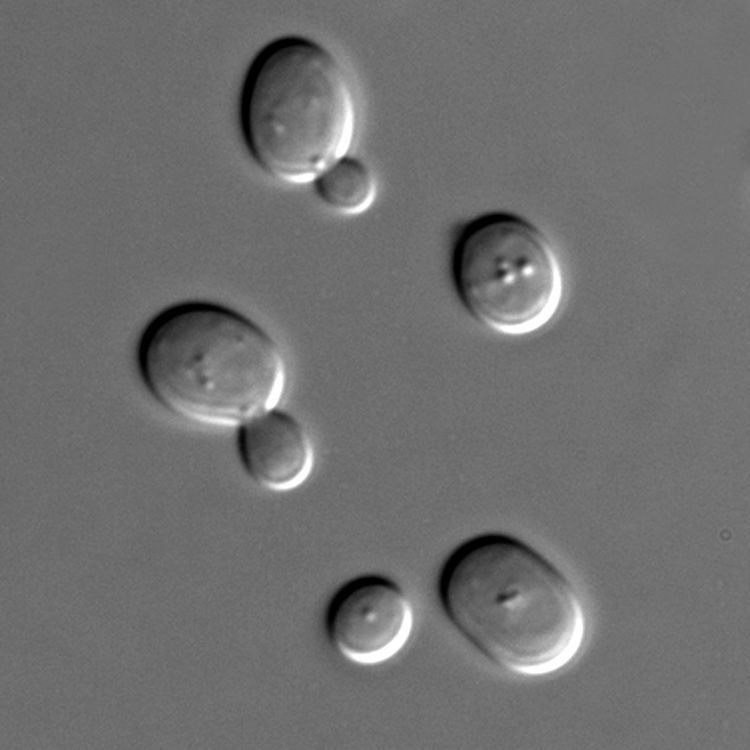

Anti-Saccharomyces cerevisiae antibodies (ASCAs) are antibodies against antigens presented by the cell wall of the yeast Saccharomyces cerevisiae. ASCAs and perinuclear antineutrophil cytoplasmic antibodies (pANCAs) are the two most useful and often discriminating biomarkers for colitis. ASCA tends to recognize Crohn's disease more frequently, whereas pANCA tend to recognize ulcerative colitis.

ASCA antibodies react to a protein called a yeast mannan, a 200-kDa glycoprotein. Diseases in which ASCA are found include the following:

Mannan (oligomannan) is a component of the yeast cell wall. Antibodies to yeast mannans are found at increased frequency in Crohn's disease and ASCA+ Crohn's tend to have lower low levels of mannan-binding lectin. Experimentally, antibodies to mannans from yeast can also crossreact to mannans of other types of yeast. Study of the sugars indicated that a mannotetraose (4-mer) was responsible for highest response. Studies of the 200 kDa glycoprotein antibodies found them commonly in healthy people, suggesting that the disease associated antibodies are to their carbohydrate moieties. Mannans from other yeast, for example candida albicans, have found to cross react with ASCA which suggests that other yeast may induce ASCA associated diseases.